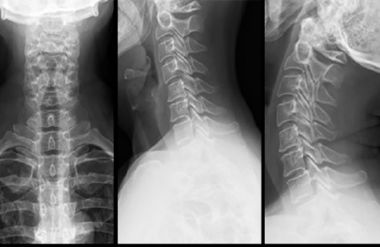

Если боль не проходит в течение 3–4 дней, необходимо сделать рентген грудного и шейного отделов позвоночника.

- Рентгенологическое исследование при подозрении на артрит, спондилолистез или нарушения осанки.